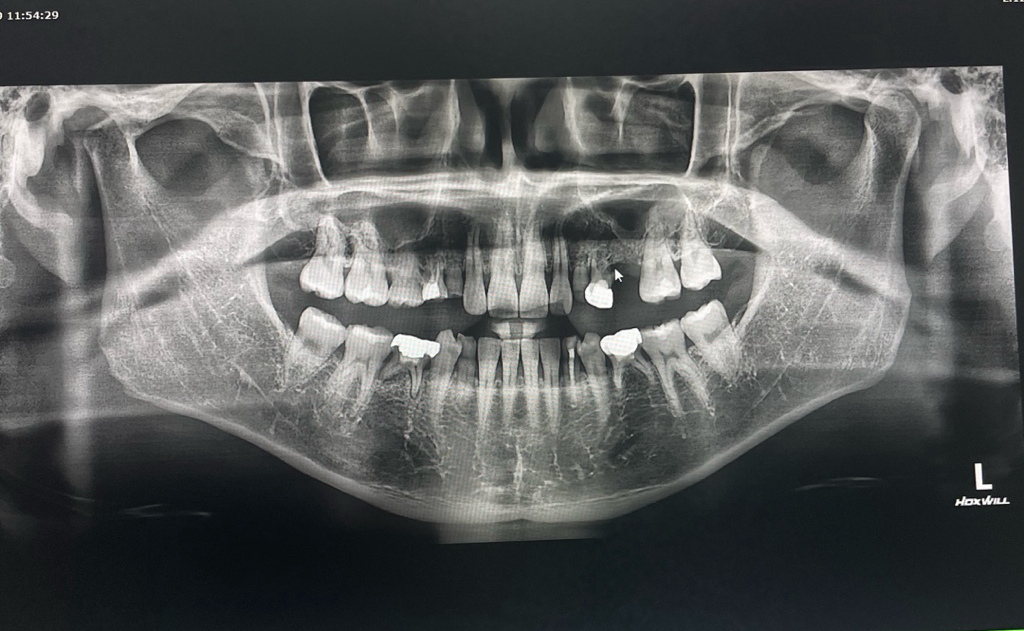

영구치가 선천적으로 결손된경우에는 유치를 최대한 오래 사용하시고 추후에 문제가 생기면 그떄는 임플란트 또는 브릿지 치료를 하시면될것같습니다.

유치는 영구치에 비해서 충치 저항성이 낮으며, 마모도 쉽게 일어납니다. 즉 시기의 문제일 뿐 시간이 지나면 유치에 문제가 생기며 발치를 해야하며 이러한 경우에 해당 부분을 수복해주는 방법은 임플란트 밖에 없습니다. 물론 앞 뒤 치아를 이용한 브릿지 등의 치료도 있습니다.

유치가 남아있다면 보통은 발치후에 임플란트를 하며 여러개인 경우 브릿지를 할 수도 있습니다.

미관상 앞니 옆 3개의 유치가 보기 좋지 않은 경우 발치를 하고 임플란트를 하거나 해당부위에 라미네이트로 치아성형을 하는 방법이 있습니다.

결손치료 인해서 해당 부위에 치아가 없다면 수복할 수 있는 방법은 임플란트나 브릿지 등으로 해서 치아를 만드는 것입니다. 브릿지는 정상적인 치아를 다듬어야 할 수 있기 때문에 임플란트가 우선적인 치료 방법이 될 수 있을 것으로 보입니다. 자세한 확인을 위해서 치과에서 진료를 받아보세요.